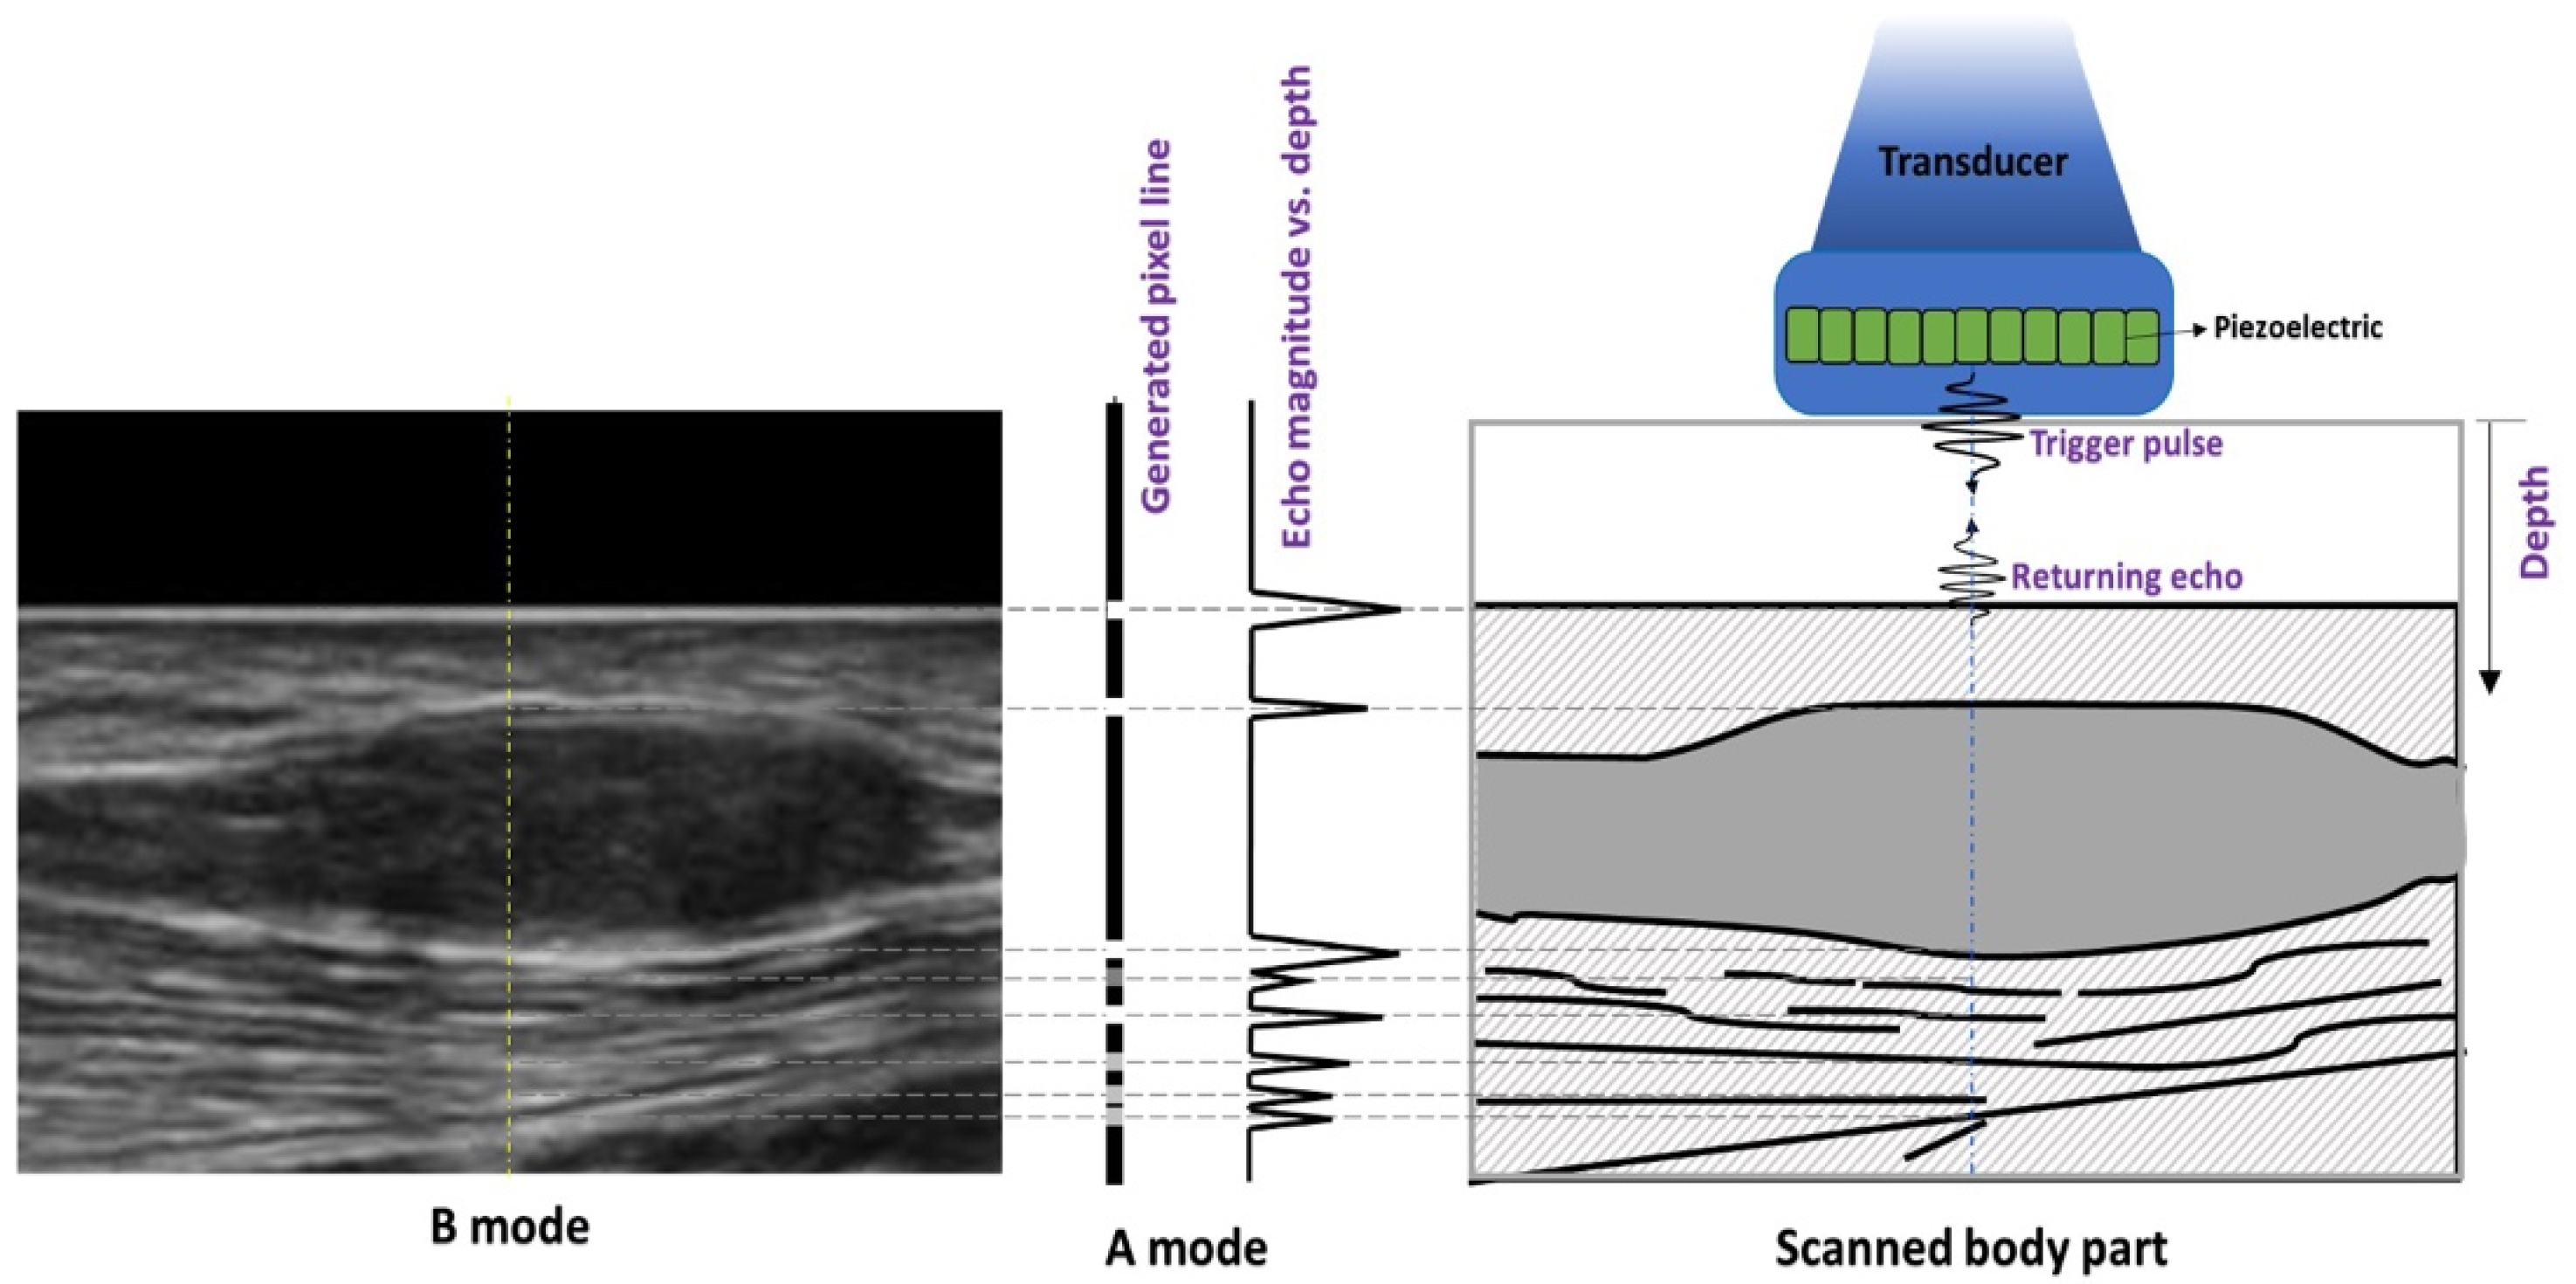

2. Normal Skeletal Muscle Anatomy on Ultrasound